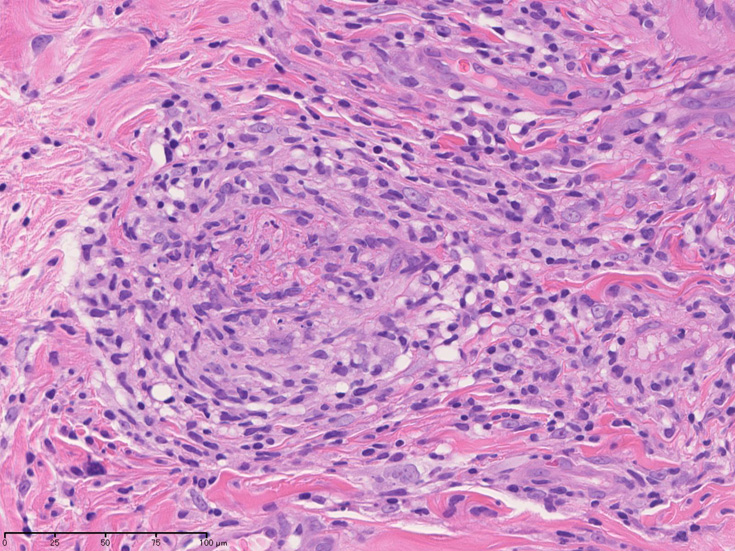

皮膚の血管(静脈・細動脈)病変、脂肪織炎 (サムネイルをクリックすると大きな画像が見られます)

Bec01.jpg

fibrinoidnecrosis01.jpg

vasculitisYa.jpg

fibrinoid necrosis

obstruction.jpg

fibrinoid necrosis(拡大)

Bec05.jpg

免疫染色:血管腔を閉塞する細胞の多くはCD68, CD163陽性細胞. CD34陽性内皮が保たれている。